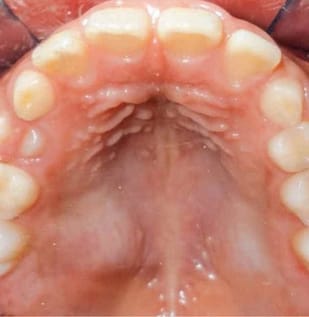

- Torus palatino: De origen desconocido y mostrando un aspecto muy similar al cuadro anterior, consiste en una masa ósea que aparece en la línea media del paladar duro, evoluciona con un crecimiento lento y se cree que pueda tener factores genéticos